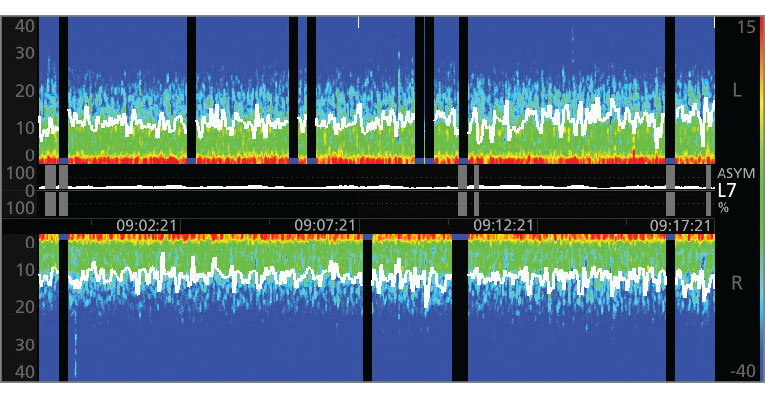

3. A Density Spectral Array (DSA) display, which contains left and right spectrograms representing the power of the EEG on both sides of the brain

The Power of the Density Spectral Array (DSA)

SedLine offers the flexibility of choosing to display either an enhanced Multitaper Density Spectral Array (DSA) or a standard Hanning DSA.

• This provides the ability to see the symmetry of left and right sides of the brain.

• Clearly indicates incidence of burst suppression/isoelectric activity as a black line with blue tip.

• Spectral edge frequency represents where 95% of the brain power lies.